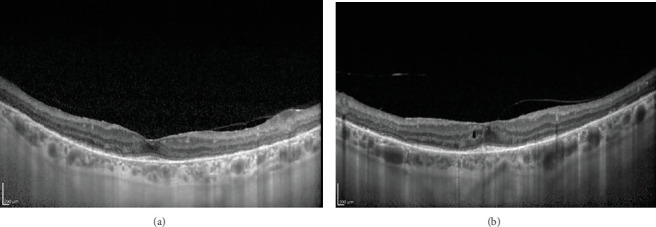

Abstract Image